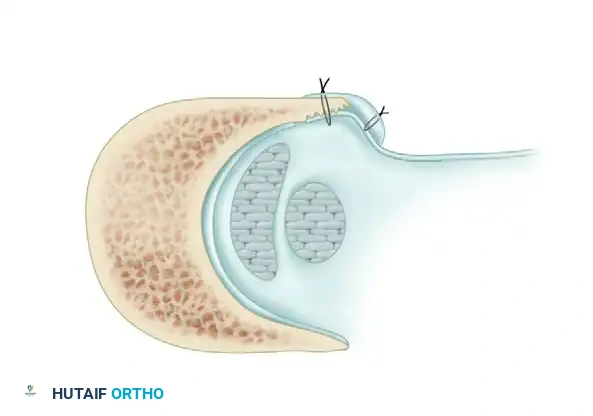

Carefully evaluate the septum that extends from the fibula to the SPR, separating the peroneus longus and brevis. An accessory peroneal tendon (peroneus quartus) may be present in a separate compartment, contributing to overcrowding and stenosis. Release this septum and inspect the peroneus brevis, looking for any accessory slips.

Inspect the tendons meticulously for attritional, longitudinal fissuring. This pathology is most commonly located on the deep (anterior) surface of the peroneus brevis tendon, where it is compressed against the fibula by the overlying peroneus longus.

If the tear involves less than 50% of the tendon's cross-sectional area, excise the smaller, degenerative section of the tendon completely. The remaining viable portion is then tubularized to restore a smooth gliding surface. This is achieved using a running 3-0 absorbable, braided suture, burying the knots to minimize friction.